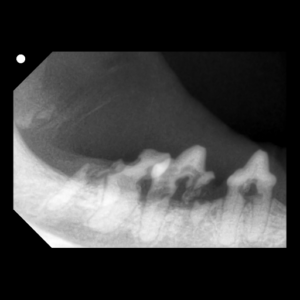

乳歯遺残が引き起こすリスクと抜歯の重要性

サークルどうぶつ病院五条です。 ワンちゃんの歯が生え変わる生後4〜7ヶ月ごろ、「新しい歯が生えてきたのに、古い歯(乳歯)が抜けない」という状態を見かけませんか?これは「乳歯遺残(晩期残存乳歯)」と呼ばれ、放っておくと将来 […]